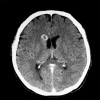

Apabila muncul gejala sakit kepala disertai tanda bahaya seperti kejang, mual, muntah, defisit neurologis seperti gangguan penglihatan, pasien harus segera dibawa ke fasilitas kesehatan terutama rumah sakit yang memiliki modalitas pencitraan seperti CT-scan atau MRI.

Pada pasien sudah terdiagnosis dengan abses otak, evaluasi hasil pengobatan melalui pemeriksaan pencitraan serial harus dilakukan untuk melihat resolusi abses.

Penyangatan pada lesi dapat diamati hingga beberapa bulan pasca terapi.  Mengenali tanda-tanda awal komplikasi dapat memberikan prognosis pasien yang lebih baik.[3,12]